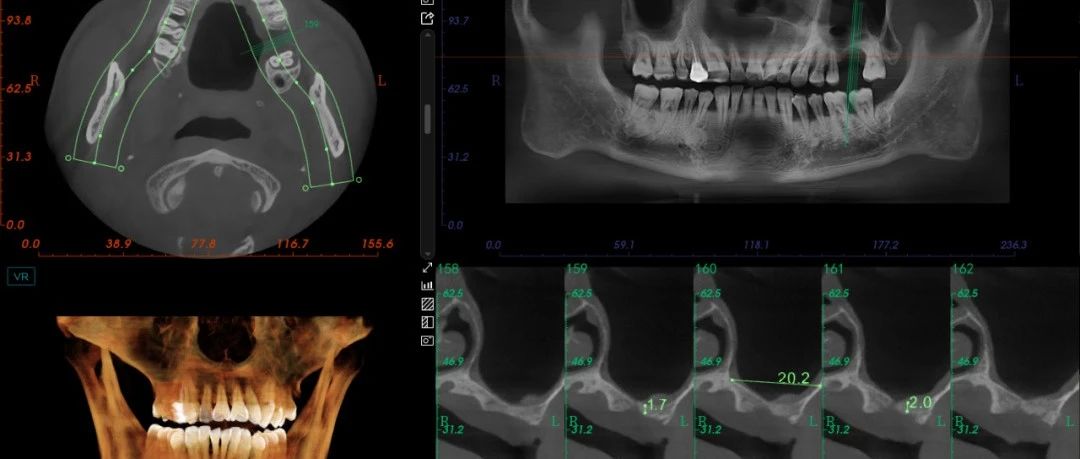

患者坚持双月维护计划,修复体功能良好,无主观不适主诉。术后4年行锥形束CT(CBCT)检查,影像学评估证实:

-

种植体周围骨结合状态稳定;

根尖区骨组织持续保持愈合状态;

未发现病理性改变(图4)

注意下颌右侧第一前磨牙的根尖神经横断。(a) 横断面图像。(b) 3D立体图。